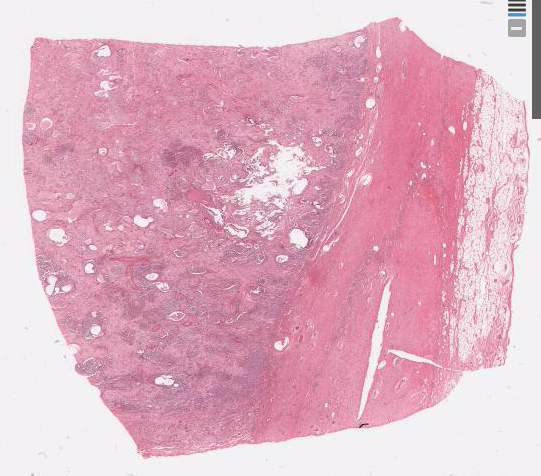

Silicosis - silicotic nodules

Asbestosis - interstitial fibrosis, pleural thickening

Asbestosis - interstitial fibrosis, calcified pleural plaques

Silicosis - perihilar lymphadenopathy, silicotic nodules

Asbestosis - interstitial fibrosis denser in lower zones, pleural fibrosis

Anthracosilicosis - upper lobe fibrosis, apical pleural thickening